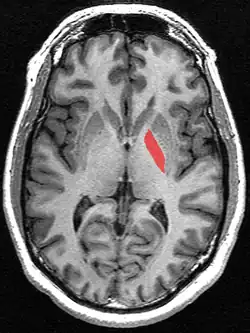

![]() Globus pallidus (in red) shown within the brain | |

The globus pallidus (GP), also known as paleostriatum or dorsal pallidum,[1] is a major component of the subcortical basal ganglia in the brain. It consists of two adjacent segments, one external (or lateral), known in rodents simply as the globus pallidus, and one internal (or medial). It is part of the telencephalon, but retains close functional ties with the subthalamus in the diencephalon – both of which are part of the extrapyramidal motor system.[2]

The globus pallidus is traversed by the numerous myelinated axons of the striatopallidonigral bundle that give it the pale appearance from which it is named.

In primates, the globus pallidus is divided into two parts by a thin medial medullary lamina.[7] These are the internal globus pallidus (GPi) and the external globus pallidus (GPe); both are composed of closed nuclei surrounded by myelinic walls.